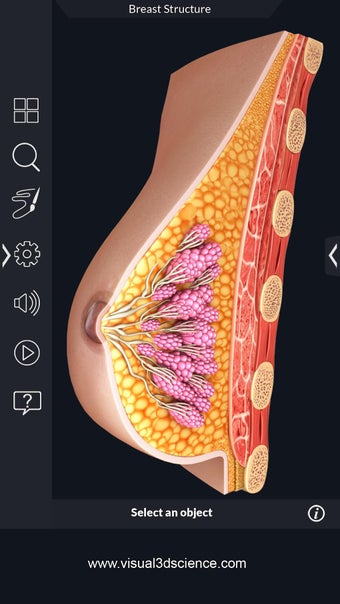

My Organs Anatomy es una aplicación de anatomía 3D gratuita desarrollada por Visual 3D Science para usuarios de Android. Esta aplicación proporciona un modelo 3D altamente realista de los órganos humanos que se puede girar 360°, acercar y alejar, y ver desde cualquier ángulo. La aplicación está diseñada para proporcionar una mirada detallada a la anatomía de los órganos humanos y ofrece varias características para ayudar a los usuarios a explorar y aprender.

La interfaz fácil de usar de My Organs Anatomy permite una navegación sencilla, lo que facilita la selección, rayos X, ocultación y visualización de órganos individuales. La aplicación también incluye un modo de animación, opciones de búsqueda y un panel de información que proporciona información relacionada. Además, la aplicación ofrece pronunciación de audio para todos los términos anatómicos, e incluso los usuarios pueden dibujar o escribir en la pantalla y compartir capturas de pantalla.

En general, My Organs Anatomy es una gran aplicación para estudiantes de medicina y cualquier persona que quiera explorar la anatomía de los órganos humanos en detalle. Con sus gráficos de alta calidad y numerosas características, esta aplicación proporciona una excelente experiencia de aprendizaje para los usuarios.